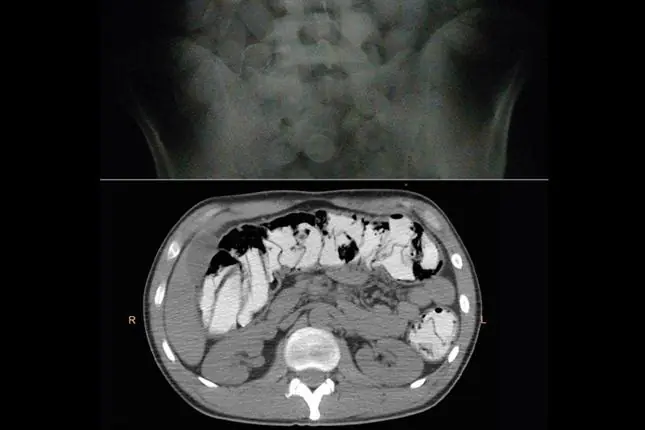

"En 2011 comenzaron a llegar personas que habían ingerido cápsulas líquidas. Éstas no son detectadas por placas, por lo que comenzamos a practicar tomografías computadas. El riesgo con la droga líquida es mayor porque, si bien es más fácil de ingerir, hay más posibilidades de que se perforen y esto puede ser letal para el paciente", explica la médica especialista.

El caso más impactante que les tocó fue el de un hombre que había ingerido 298 cápsulas. "Fue terrible porque fue difícil diagnosticarlo. Cuando nos dijo que eran más de 200 fue un shock. Pero lo más difícil fue darlo de alta, porque después de tantas evacuaciones y comidas no podíamos distinguir qué había en su organismo con una placa normal. Ahí comenzamos a usar la tomografía computada", relata Sorrentino.